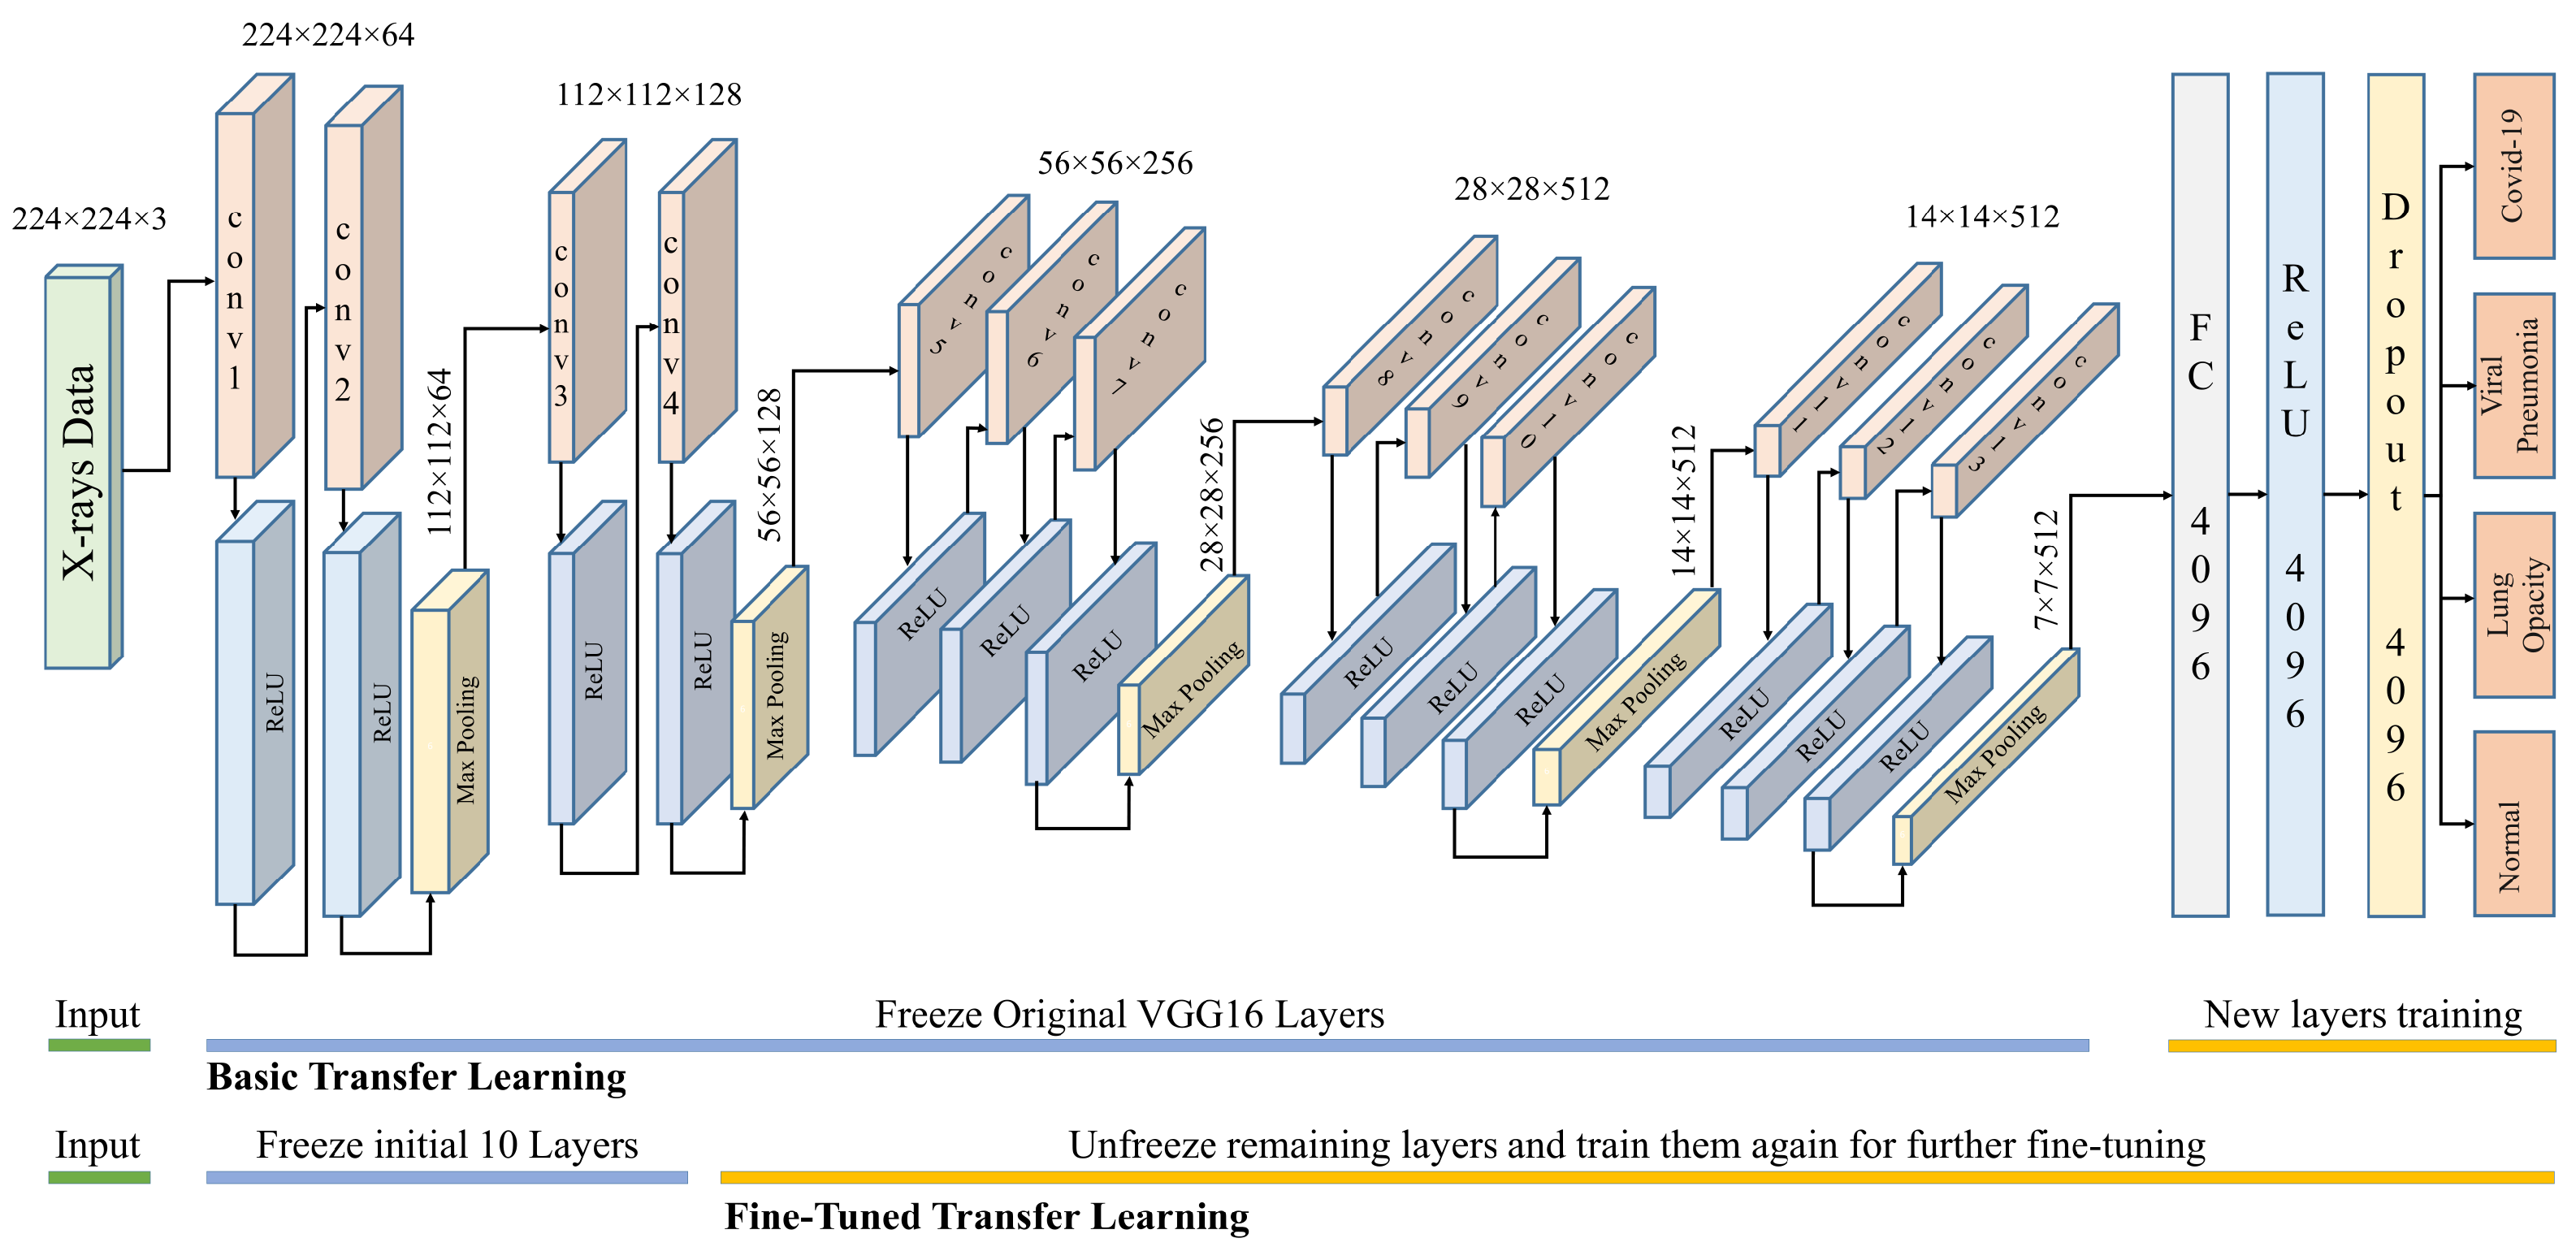

VGG16 and VGG19 are CNN-based architectures that were proposed for the classification of large-scale visual data. These architectures use small convolution filters to increase network depth. The inputs to these networks are fixed size 224 × 224 images with three color channels. The input is given to a series of convolutional layers with small receptive fields (3 × 3) and max pool layers as shown in

Figure 6. The first two sets of VGG use two conv3-64 and conv3-128, respectively, with a ReLU activation function. The last three sets use three conv3-256, conv3-512, and conv3-512, respectively, with a ReLU activation function.

Each set of convolutional layers is followed by a max-pooling layer with stride 2 and window 2 × 2. The number of channels in the convolutional layers is varied between 64 to 512. The VGG19 architecture is the same except that it has 16 convolutional layers. The final layer is a fully connected layer with four outputs corresponding to four classes. AlexNet is an extension of LeNet, with a much deeper architecture. It has a total of eight layers, five convolution layers, and three fully connected layers. All layers are connected to a ReLU activation function. AlexNet uses data augmentation and drop-out techniques to avoid overfitting problems that could arise because of excessive parameters. DenseNet can be thought of as a extension of ResNet, where the output of a previous layer is added to a subsequent layer. DenseNet proposed concatenation of the outputs of previous layers with subsequent layers. Concatenation enhances the distinction in the input of succeeding layers thereby increasing efficiency. DenseNet considerably decreases the number of parameters in the learned model. For this research, the DenseNet-201 architecture is used. It has four dense blocks, each of which is followed by a transition layer, except the last block, which is followed by a classification layer. A dense block contains several sets of 1 × 1 and 3 × 3 convolutional layers. A transition block contains a 1 × 1 convolutional layer and 2 × 2 average pooling layer. The classification layer contains a 7 × 7 global average pool, followed by a fully connected network with four outputs. GoogleNet architecture is based on inception modules, which have convolution operations with different filter sizes working at the same level. This basically increases the width of the network as well. The architecture consists of 27 layers (22 layers with parameters) with 9 stacked inception modules. At the end of inception modules, a fully connected layer with the SoftMax loss function works as the classifier for the 4 classes.

Training the above-mentioned models from scratch requires computation and data resources. Probably, a better approach is to adopt transfer learning in one experimental setting and to reuse it for other similar settings. Transferring all learned weights as it is may not perform well in the new setting. Thus, it is better to freeze the initial layers and replace the latter layers with random initializations. This partially altered model is retrained on the current dataset to learn the new data classes. The number of layers that are frozen or fine-tuned depends on the available dataset and computational power. If sufficient data and computation power are available, then we can unfreeze more layers and fine-tune them for the specific problem.

For this research, we used two levels of fine-tuning: (1) freeze all feature extraction layers and unfreeze the fully connected layers where classification decisions are made; (2) freeze initial feature extraction layers and unfreeze the latter feature extraction and fully connected layers. The latter is expected to produce better results but needs more training time and data. For VGG16 in case 2, only the initial 10 layers are frozen, and the rest of the layers were retrained for fine-tuning.